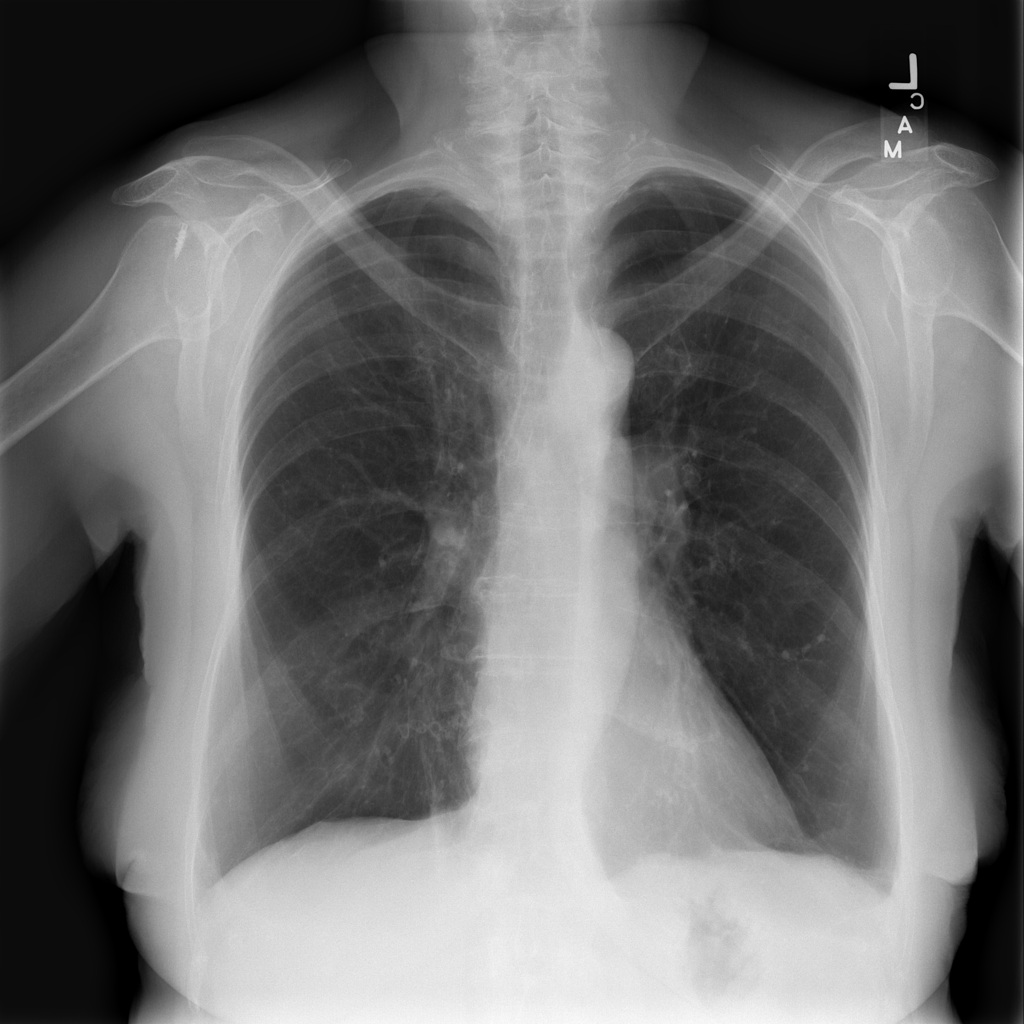

PAT-B625 · IMG-011Atelectasis

PAT-B625 · IMG-011

PA